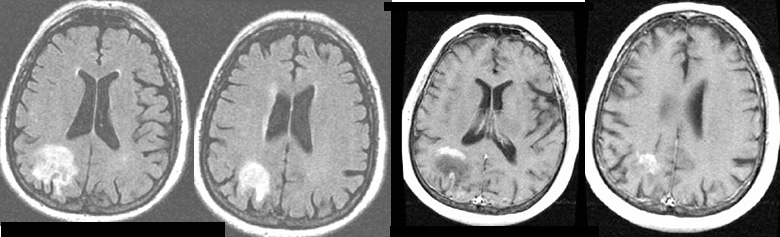

Tumoral edema. B,The tumor shows heterogeneous enhancement after intravenous injection of con-trast medium. AJNR: 22, June/July 2001 BRAIN TUMOR 1085 FIG 4. Meningothelial meningioma in the left high frontal convexity. A, On a T2-weighted image, tumor is mildly high in intensity. ... Retrieve Content